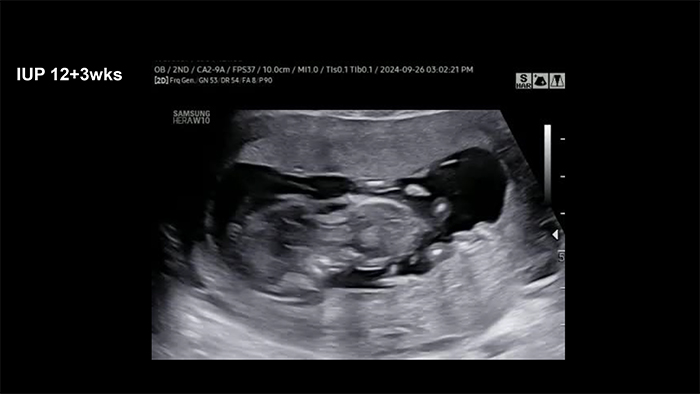

The initial ultrasonography showed weird extremities of the fetus. After that, the clinician diagnosed a conjoined twin with hydrops: one head, one heart, one liver, four arms, and four legs.

Gross examination of the abortus revealed the top of the head down to the belly button, facing each other (cephalopagus).